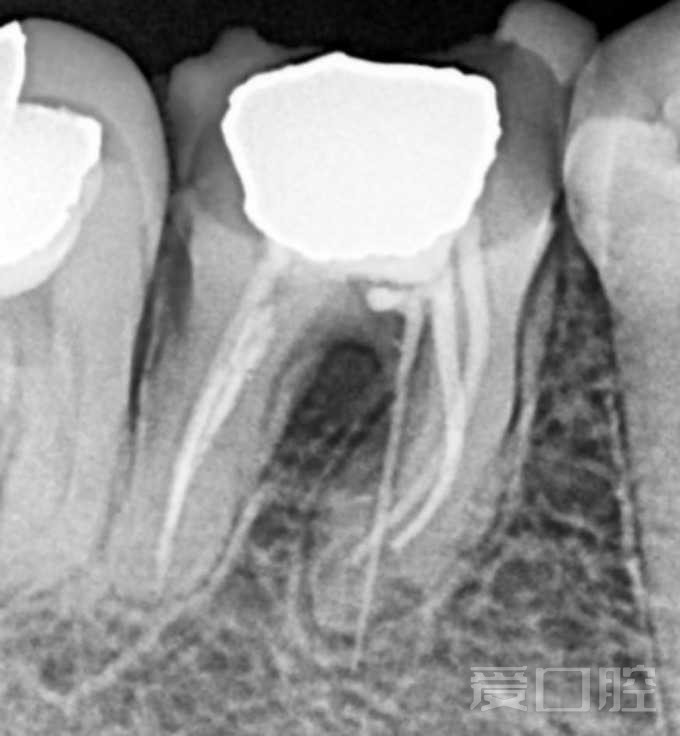

看个根管在治疗+穿孔修复 —— 下6